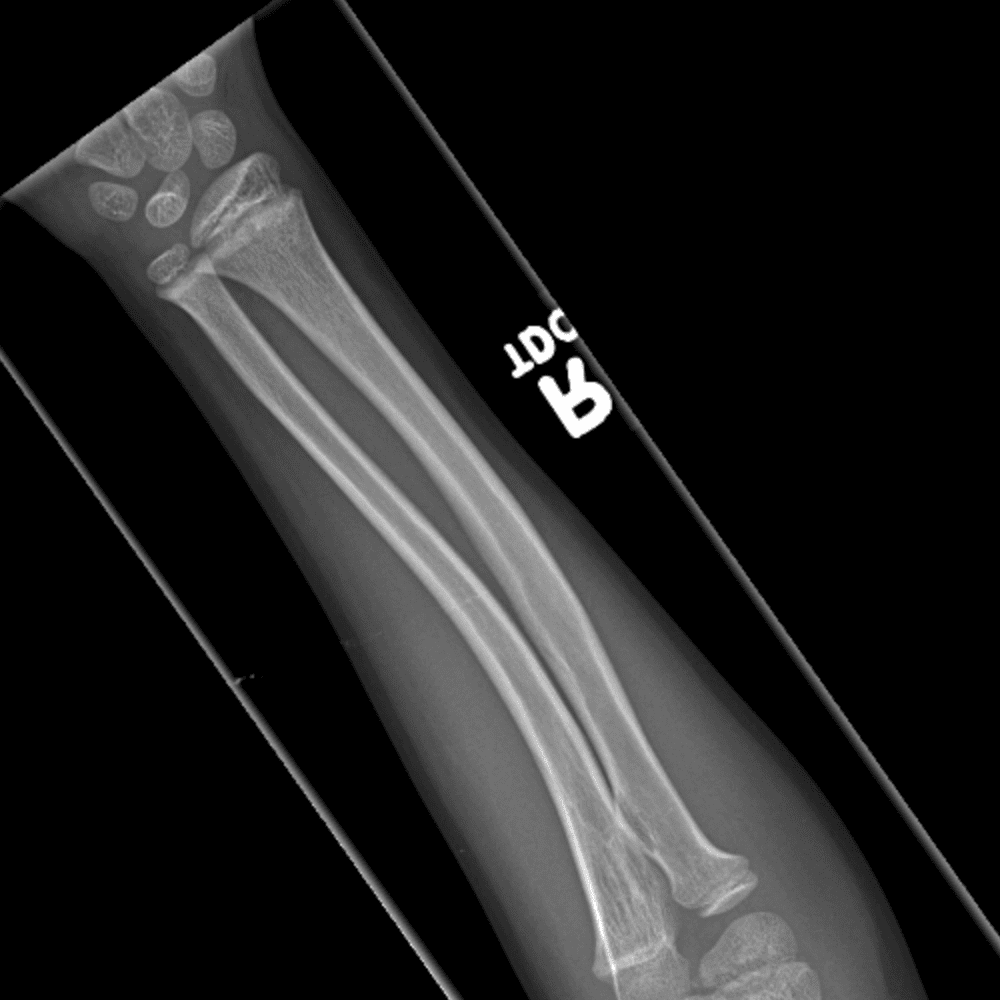

Simulates call by including subtle or difficult cases and some normals.

30 cases